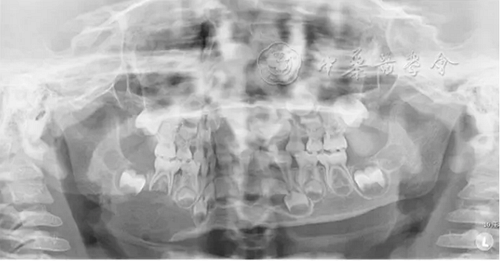

(1)疾病定義及口腔表現(xiàn):中性粒細胞減少是由于外周血中粒細胞的絕對值減少而出現(xiàn)的一組綜合征。出生后2周至1歲的嬰幼兒中性粒細胞低于1×109/L、1歲以上兒童中性粒細胞低于1.5×109/L時,即可診斷為中性粒細胞減少癥。當中性粒細胞低于0.5×109/L時則可診斷為粒細胞缺乏(agranulocytosis)。根據(jù)中性粒細胞減少的程度和持續(xù)時間,病情的輕重不同。病程初期為發(fā)熱,之后表現(xiàn)為反復感染且難以控制,好發(fā)于呼吸道、泌尿系、皮膚和黏膜等。在口腔主要表現(xiàn)為反復發(fā)作的口腔炎、口腔潰瘍,牙齒松動、乳牙早失,牙齦紅腫、糜爛、齦袋溢膿及牙槽骨喪失等(圖1)。

圖1 4歲中性粒細胞減少患兒乳牙牙齦明顯紅腫、糜爛